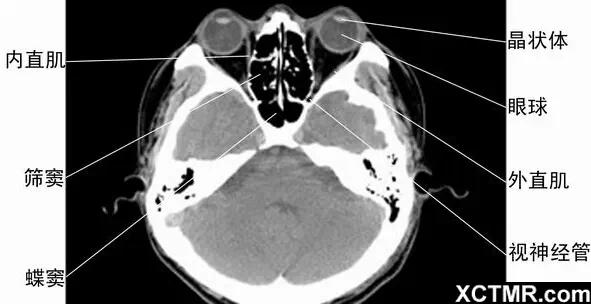

5眼眶橫斷面-CT - 解剖圖片

頭頸五官CT斷層解剖圖及常見病影像診斷